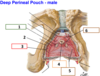

3? 4?

3? 4? 5?

3: Crus

4: Bulb of the vestibule